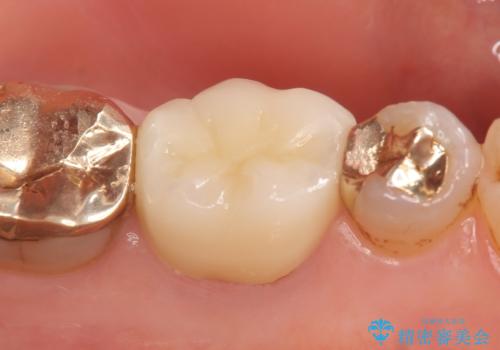

その後症状の消失を確認し、オールセラミッククラウンによる補綴を行いました。

今回用いたオールセラミッククラウンはジルコニアフレームという白い素材の上にセラミックを盛っているため、審美性が非常に高いのが特徴です。

また、ジルコニアは人工ダイヤモンドの材料にも使われているほど高い強度を持っており、そのためオールセラミッククラウンは審美性だけでなく、奥歯やブリッジの補綴も可能とするクラウンです。